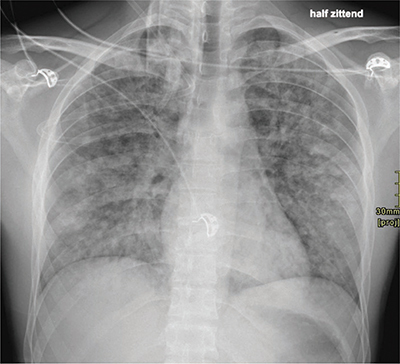

A case of complete recovery of negative pressure pulmonary edema after a Cottle surgery in a 24-year-old male. Teaching point: Negative pressure pulmonary edema is an important cause of postoperative noncardiogenic edema, with the spontaneous disappearance of all complaints within a relatively short period.

Abstract Image